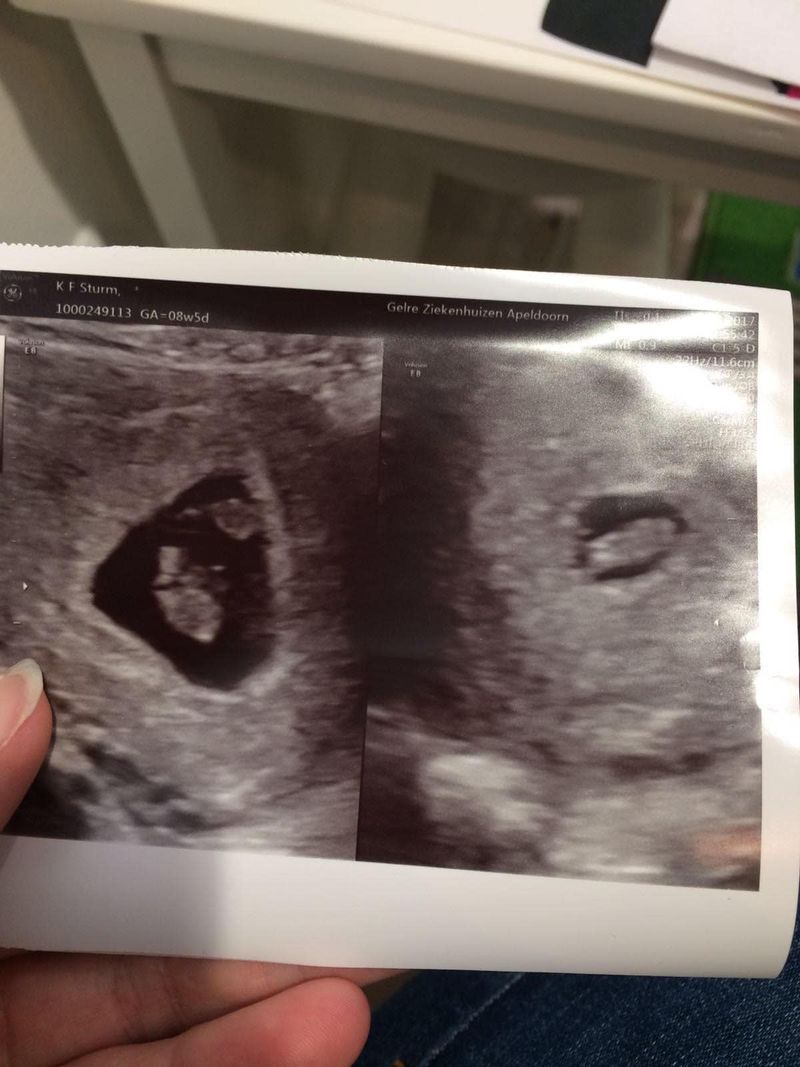

Ik belde gelijk de verloskundige en kon een aantal dagen later al komen. Daar zagen we gelijk een mooi kloppend hartje en ik was dus al dik acht weken zwanger. We moesten even wennen en ik dacht ook wel: “Kan mijn lichaam dit wel aan, gaat het allemaal wel goed met het litteken?”. Deze baby zou komen voordat onze dochter Maud 15 maanden was. Ze zaten echt dicht op elkaar.